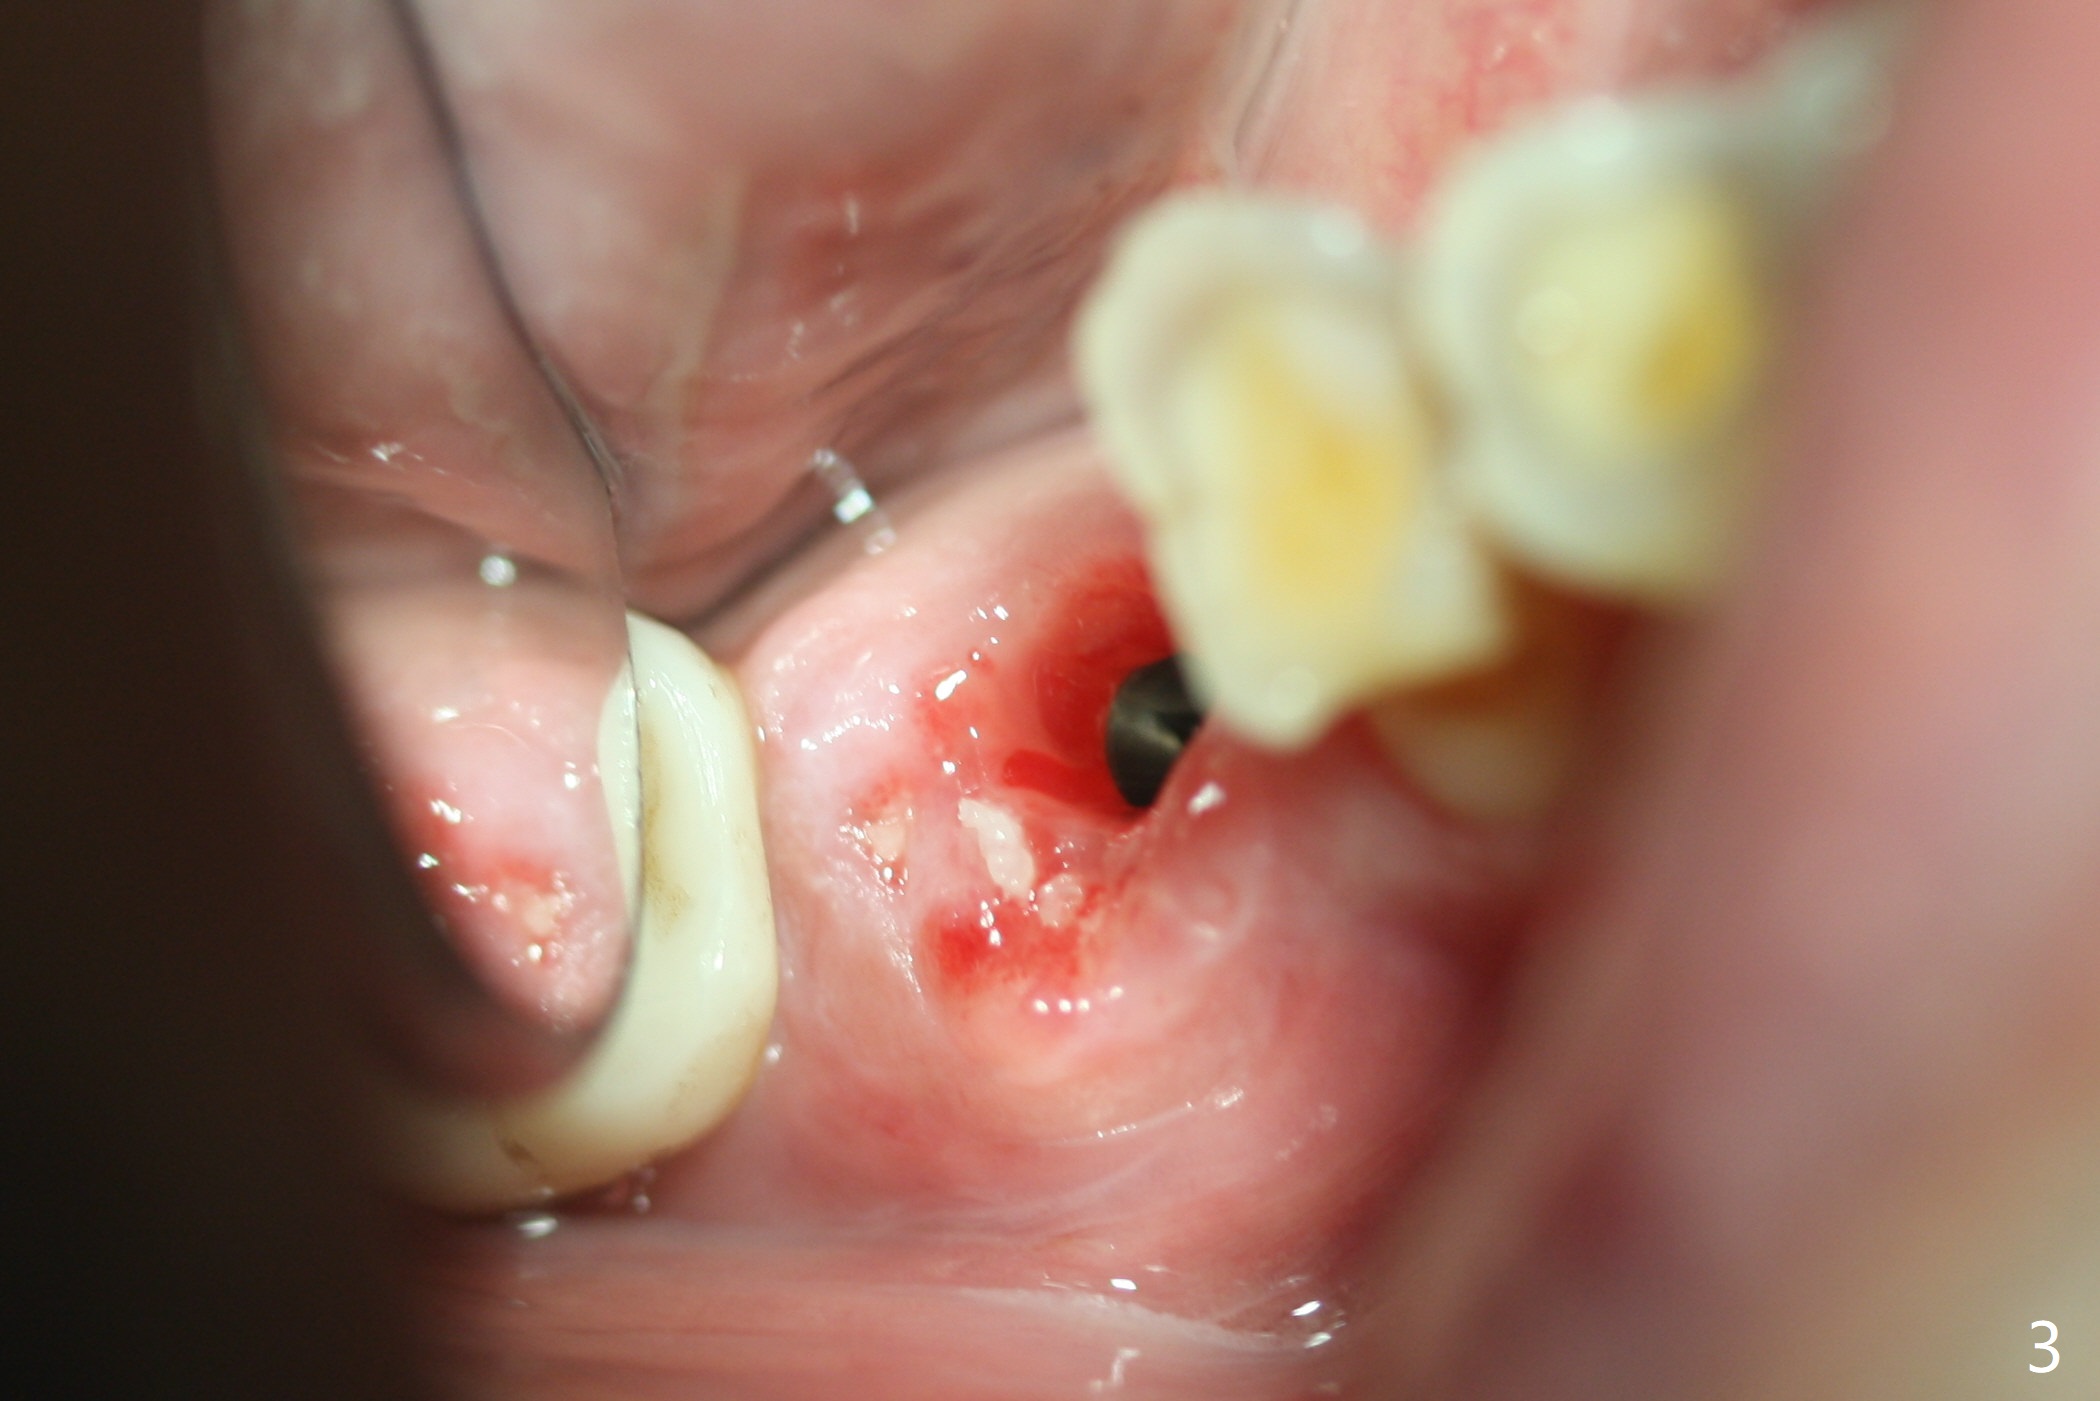

Vertical fracture of the mesial root of the tooth #30 after RCT is associated with bone loss (Fig.00 *). When the mesial portion of the mesial root (M', loose one) is exfoliated, the bone loss resolves (Fig.0). To reduce heat-induced bone necrosis at #19, osteotomy is conducted slowly with copious irrigation with cold saline. Bone density is felt while a 5x10 mm implant is being placed after using cortical tap to the 2nd line of the implant driver. The implant needs to be reverse torqued several times before reaching its final depth (Fig.1 (~50 Ncm)). Since the residual roots are superficially positioned, the immediate implant looks as a delayed one. Although the implant is placed mesial to the septum clinically, its position in X-ray seems to be normal. Because of severe wear and lack of vertical height, a 6.8x5 mm healing abutment is placed. Retention of bone graft (Fig.1 *) is maintained by spreading setting acrylic into the edentulous undercut areas (Fig.2 *). The so called "acrylic dressing" remains in place 3 weeks postop (Fig.8). When it is removed with the healing abutment, the wound heals (Fig.3). Note the limited vertical height. The bone graft placed in the distal socket appears to have been converted to the native bone 3.5 months postop (Fig.4). To reduce severe wear of the natural teeth, the occlusion of the new crown is not heavily decreased (Fig.5). It should be alright considering favorable crown/implant ratio (Fig.6). There is no bone loss 5 months post cementation, although the abutment screw is just retightened (Fig.7). In spite of poor trajectory associated with #18 (Fig.8) and 31 (Fig.7) Bicon implants, the abutments have not been dislodged. For the bruxer, the next implant at #19 with distal root fracture (Fig.8 ^) should be Bicon. The patient complains of food impaction nearly 1 year post cementation. The mesial and distal contacts of #30 crowns are light. When the abutment/crown is removed, there is implant well contamination (food debris). It appears that the previous abutment (5.7x4(2) mm, Fig.6,7) is incompletely seated. When a smaller abutment is placed and torqued at 30 Ncm, it is seated fully (Fig.9 (<: no gap)). New impression is taken. The distal gingival embrasure is larger than the mesial one because of the higher distal crest (Fig.6,7). If there is food impaction distal to the new crown, the distal crestal bone should be removed with lab closure of the embrasure.